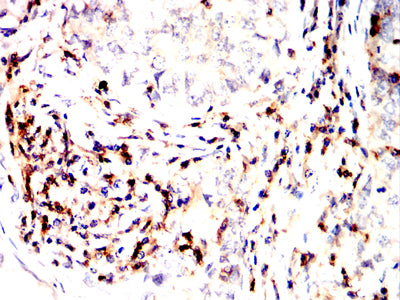

分类: 科研抗体货号: 32332别名: SCDO1应用: IHC,FCM反应种属: Human